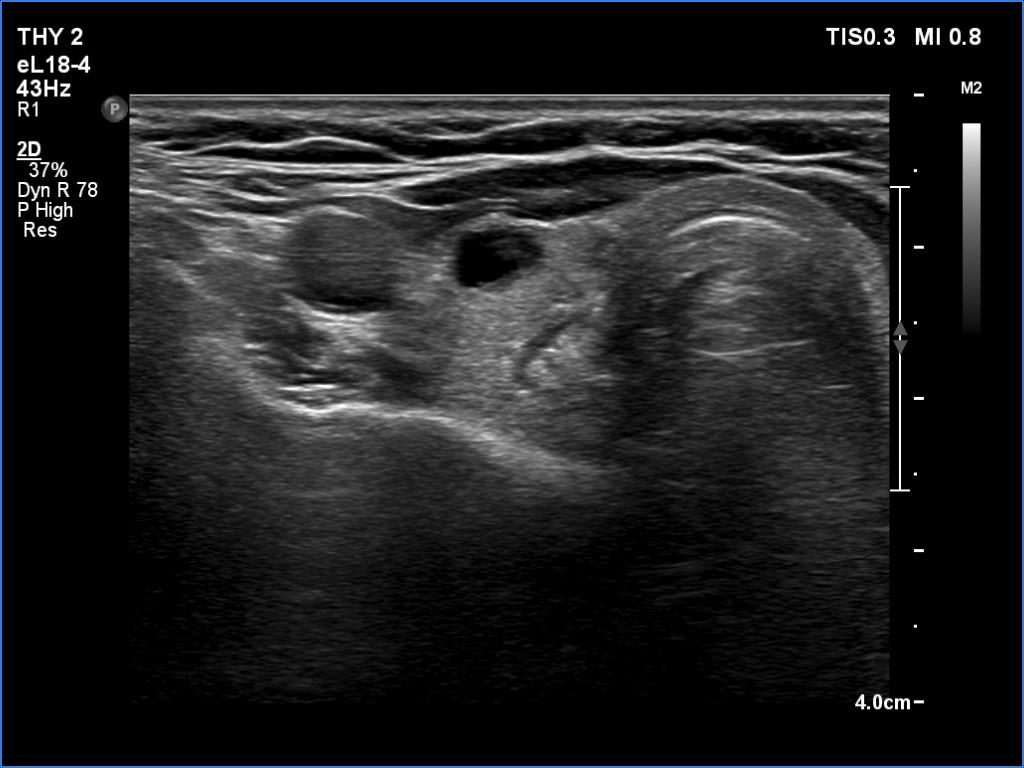

Second examination 6 month later (2nd row of images)

Clinical presentation. The patient was referred for evaluation of hyperparathyroidism. Elevated calcium and parathyroid hormone levels were found during the first evaluation. (These findings were not yet available when I first examined the patient.) Further evaluation disclosed a hyperfunctioning right lower parathyroid. The patient was operated on but no parathyroid tissue was found on histopathology. (A more experienced parathyroid surgeon was quarantined at the scheduled time of the operation, so a less experienced colleague performed the surgery.) Both hypercalcemia and hyperparathyroidism have persisted.

Palpation: no abnormality.

Laboratory tests: parathormone 129 pg/ml (normal value: 12-88), serum calcium 2,89 mM/L, phosphate 0,71 mM/L.

Ultrasonography revealed a hypoechoic mass corresponding to the right lower parathyroid.

Cytology resulted in benign lesion, a pattern which corresponded to a parathyroid adenoma.

The patient was reoperated and histopathology disclosed a parathyroid adenoma according to the right lower parathyroid.